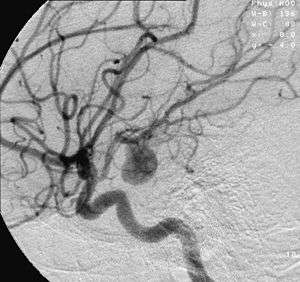

- Focal cerebral ischemia – A stroke occurring in a localized area that can either be acute or transient. This may be due to a variety of medical conditions such as an aneurysm that causes a hemorrhagic stroke, or an occlusion occurring in the affected blood vessels due to a thrombus (thrombotic stroke) or embolus (embolic stroke).[10] Focal cerebral ischemia constitutes a large majority of the clinical cases in stroke pathology with the infarct usually occurring in the middle cerebral artery (MCA).[11]

- Ischemic hypoxia ( or "stagnant hypoxia") – Reduced brain oxygen is caused by inadequate blood flow to the brain. Stroke, shock, cardiac arrest and heart attack may cause stagnant hypoxia. Ischemic hypoxia can also be created by pressure on the brain. Cerebral edema, brain hemorrhages and hydrocephalus exert pressure on brain tissue and impede their absorption of oxygen.